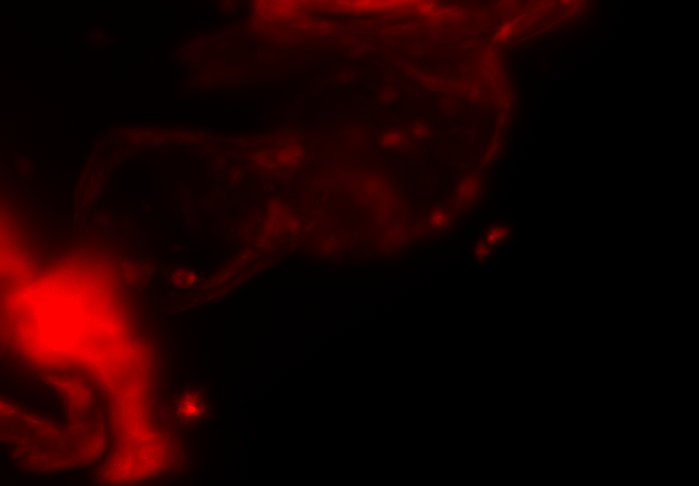

The combination of prospective optical gating for real-time phase matching and prospective optical gating for long-term phase locking allow us to capture in phase images over extended periods of times. Figure 4 demonstrates this phase locking over 18+ hours across a key developmental phase - heart looping.